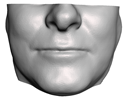

2.5.2. Soft Tissue

2.6. Textured Output Visualization

- Chin. Overall, the amount of error at the chin area is very low. This could be explained by the fact that the skin at the chin is very thin, and the coupling to the mandible makes the simulation highly predictive.

- Lips. In other regions, such as the lips, skin slides strongly over the underlying bones and teeth, and the deformation result is more difficult to predict. Overall, we observe higher variability in the error at the lips, and also some patients with higher error.

- Nose. The quality of the prediction of the deformation of the nose varies strongly across patients. In this case, the variability may depend on the type of surgery performed on each patient’s anterior nasal spine. This type of surgery is not easy to identify in the post-operative CBCT image due to the presence of bone grafts or fixation plates.

- Neck. Finally, we observe large error in the neck area (e.g., patients M5 and M8), and specifically at the junction point between the submental area and the neck (“C point” or “cervical point” in cephalometric analysis). This error was accounted for in our quantitative analysis, which negatively biased the overall results. However, this area is not of special interest to orthognathic surgeons. The deformation is known to be produced by a retraction of skin after surgery, but surgeons do not account for this effect during pre-operative planning.